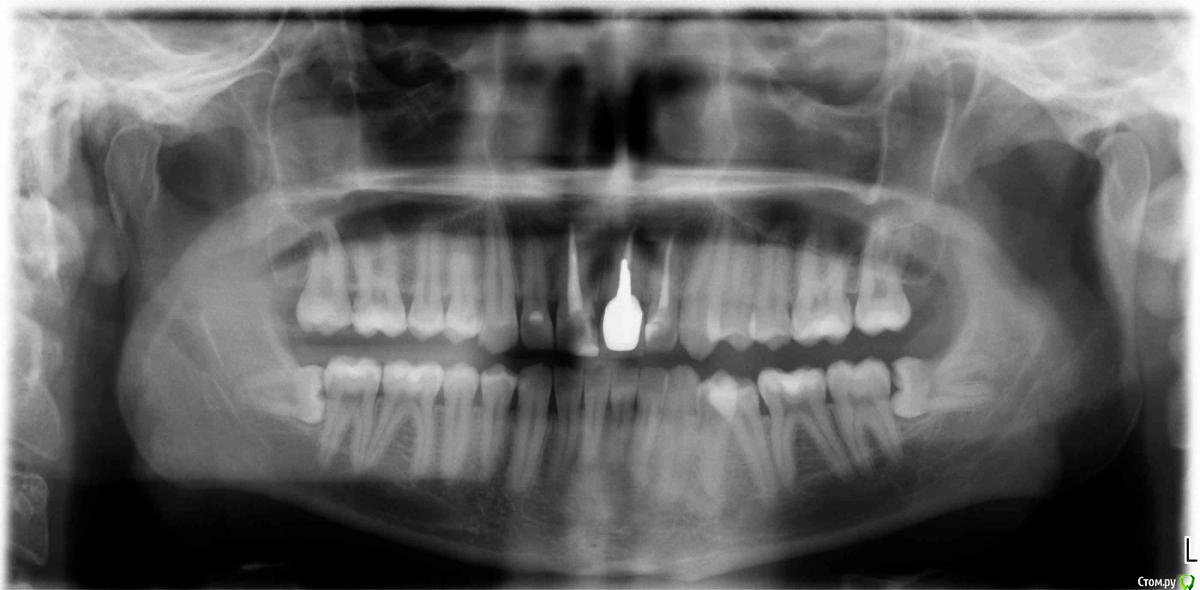

Доброй ночи, такая ситуация, 3 года назад поставили коронку единичка, 9 июля начала болеть десна там где эта коронка, сказали воспалился сосочек десны, полоскал и мазал специальной пастой 20 июля перестало болеть, 4 сентября опять начало болеть причем намного сильнее, пошел к стоматологу он сказал не страшно прописал нимисин и пасту, боль стала невыносимой и заметил, что коронка опустилось чу чуть, пошел к другому стоматологу сделали снимок и стучал по зубам больно очень было 2-ке, сказал пульпит на ней и удалил пульпу, про коронку сказал, что не поменять коронка так и будет, но проблема в том, что жевать не могу нажимаю на коронку и десне больно и она ходит чу чуть, можно ли ее снять и заного одеть?

Снимки фото прилагаю.